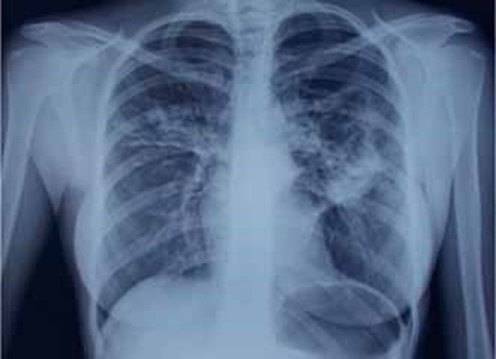

Заболела остро 14.09.15, когда появились описанные жалобы и повышение температуры до 39,6 °С. Лечилась самостоятельно (парацетамол, бромгексин) – без эффекта. Обратилась в поликлинику, где 17.09.15 выполнена обзорная рентгенография (РГ) органов грудной клетки (ОГК) (рис. 1)(О.В.Фатенков с соавт., 2018)

в верхних долях обоих легких – хлопьевидные участки неоднородной инфильтрации в S3 верхней доли с распадом и формированием полостей слева. Корни инфильтрированы. Диафрагма и синусы не изменены. Междолевая плевра слева подчеркнута.